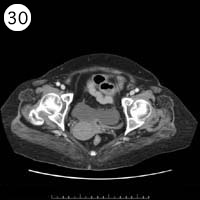

57歳 女性

単純CT

造影CT